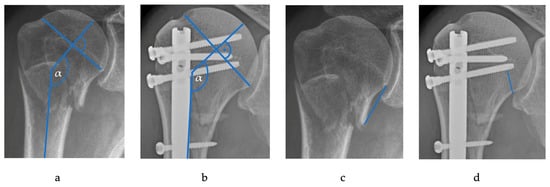

| Medial hinge: | ||

| Intact hinge; n (%) | 21 (16.2%) | 94 (72.3%) |

| Disrupted hinge; n (%) | 109 (83.8%) | 36 (27.5%) |

| Osteonecrosis of the humeral head | ||

| IH; n (%) vs. DH; n (%): | 9 (9%) vs. 0 (0%) | 7 (19.4%) vs. 2 (2.1%) |

| Fisher exact test’s p-value * | 0.335 | 0.002 |

| Risk for OHN if disruption of the medial hinge: | ||

| OR | N/A | 11.4 |

| RR | N/A | 17.6 |

| RD | 9% | 17.3% |